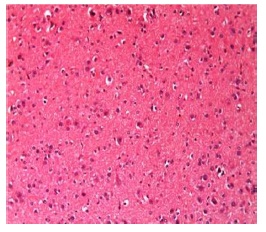

Figure 4: Histopathological examination of control group with normal neuron cells and nerve fibres.

Concerning the histopathological findings, sections of normal controlled groups showed that the cerebral cortex exhibits normal neurons surrounded by nerve fibers and blood vessels (Figure 4). In LPS induced AD neuroinflammatory rats, an observed multiple plaques formed of lamellated fibrils. Such plaques were surrounded by multiple apoptotic nuclei (Figure 5). Severe inflammation with congested blood vessels was also observed with deposits of amyloid material in their wall and surrounded by extravasated red blood corpuscles when compared with the normal control group (Figure 6). Administration of MSCs showed less dense plaques, multiple and less prominent apoptotic nuclei (Figure 7). On the other hand, administration of milk kefir grains revealed disappearance of multiple plaques, some dense plaques with few apoptotic nuclei (Figure 8). MSCs and milk kefir grains administration lead to slight focal plaques formation, multiple apoptotic nuclei with slight congestion in blood vessels (Figure 9). On the prophylaxis group, there was a slight focal plaques formation, few multiple apoptotic nuclei with less diffused congestion in blood vessels (Figure 10).